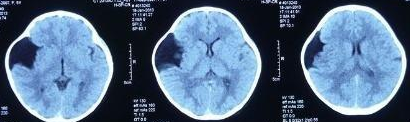

CT如图所示: